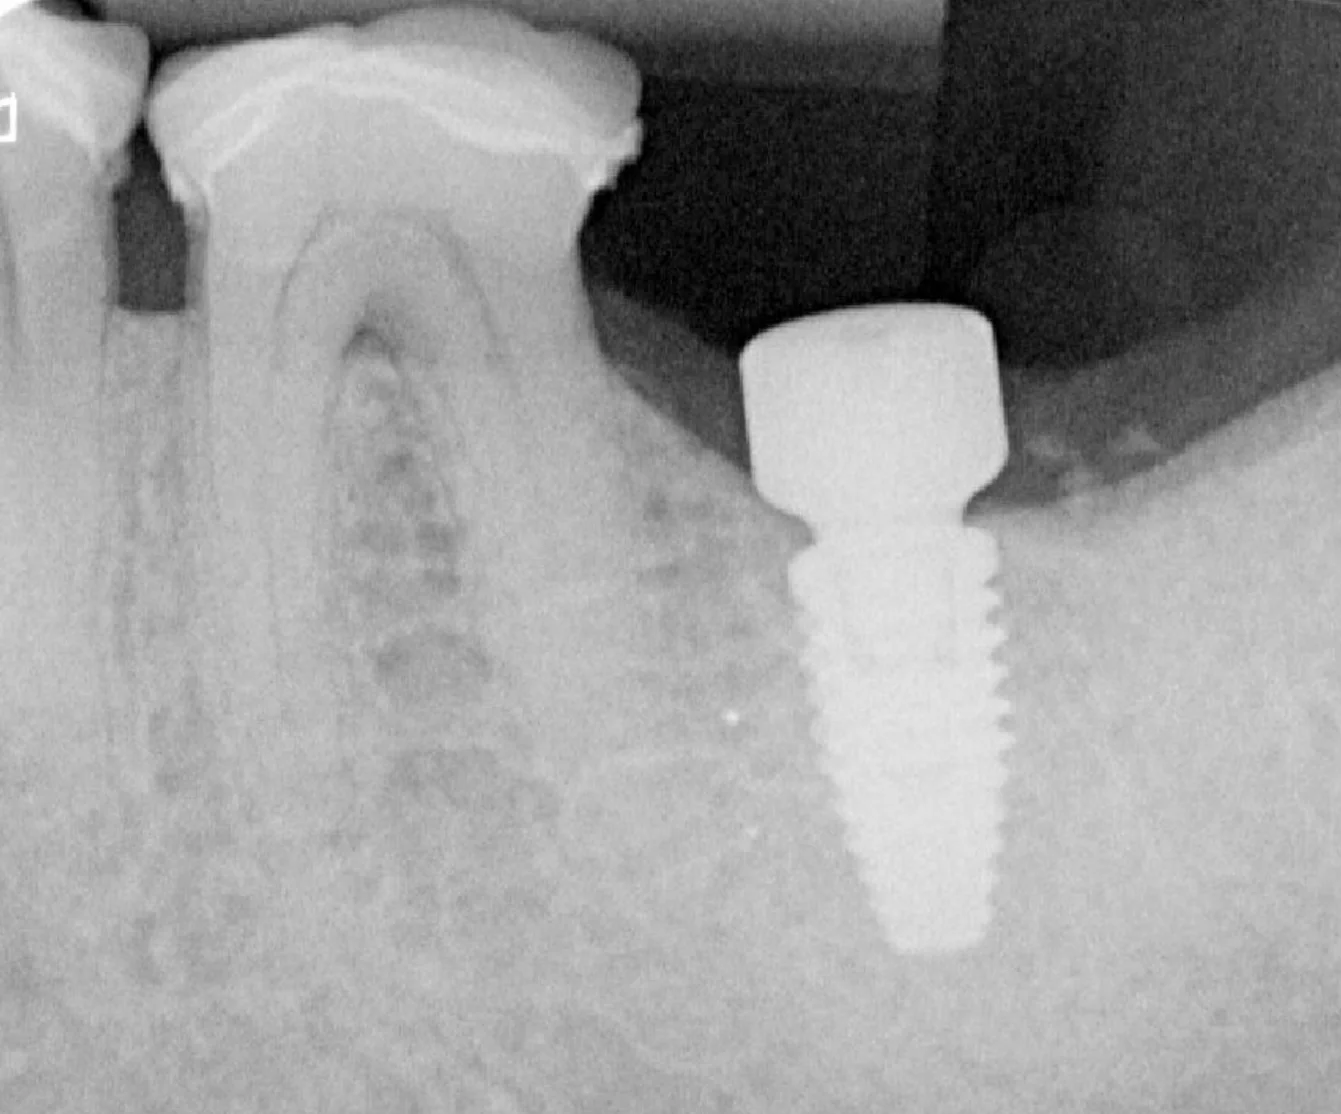

Un Cone Beam 3D est systématiquement réalisé pour analyser avec précision la quantité et la qualité osseuse disponible au site implantaire, ainsi que pour repérer les structures anatomiques à respecter (nerf alvéolaire inférieur, sinus maxillaire, etc.).

À partir des données recueillies lors de la première consultation ( Cone Beam 3D, empreinte optique, examen clinique et anamnèse médicale ) une planification implantaire tridimensionnelle est réalisée à l’aide de logiciels spécialisés.

- Positionner virtuellement l’implant de manière idéale, en respectant à la fois les contraintes anatomiques (canal mandibulaire, sinus, racines adjacentes, structures nerveuses) et les contraintes prothétiques (axe d’émergence, espace disponible, équilibre occlusal, esthétique) ;

Ce dispositif permet de localiser avec précision non seulement l’os disponible, mais aussi les structures critiques telles que le nerf alvéolaire inférieur, le sinus maxillaire ou les racines des dents voisines, assurant une pose plus sûre, plus précise et conforme au projet prothétique.